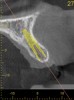

Fig 2. CBCT images: axial (Fig 2) and cross-sectional (Fig 3) views, and 3D reconstruction view (Fig 4) with virtually planned implant Nos. 8 and 9.

Fig 3. CBCT images: axial (Fig 2) and cross-sectional (Fig 3) views, and 3D reconstruction view (Fig 4) with virtually planned implant Nos. 8 and 9.

Fig 4. CBCT images: axial (Fig 2) and cross-sectional (Fig 3) views, and 3D reconstruction view (Fig 4) with virtually planned implant Nos. 8 and 9.

Fig 12. Virtual planning of a posterior implant (Fig 12) resulted in inadequate restorative running room for the crown emergence profile in the cross-sectional CBCT image. Revision (Fig 13) resulted in deeper positioning of the implant for restorative running room but necessitated transcrestal sinus elevation, possibly with the addition of bone via the osteotomy to tent the membrane.

Fig 13. Virtual planning of a posterior implant (Fig 12) resulted in inadequate restorative running room for the crown emergence profile in the cross-sectional CBCT image. Revision (Fig 13) resulted in deeper positioning of the implant for restorative running room but necessitated transcrestal sinus elevation, possibly with the addition of bone via the osteotomy to tent the membrane.